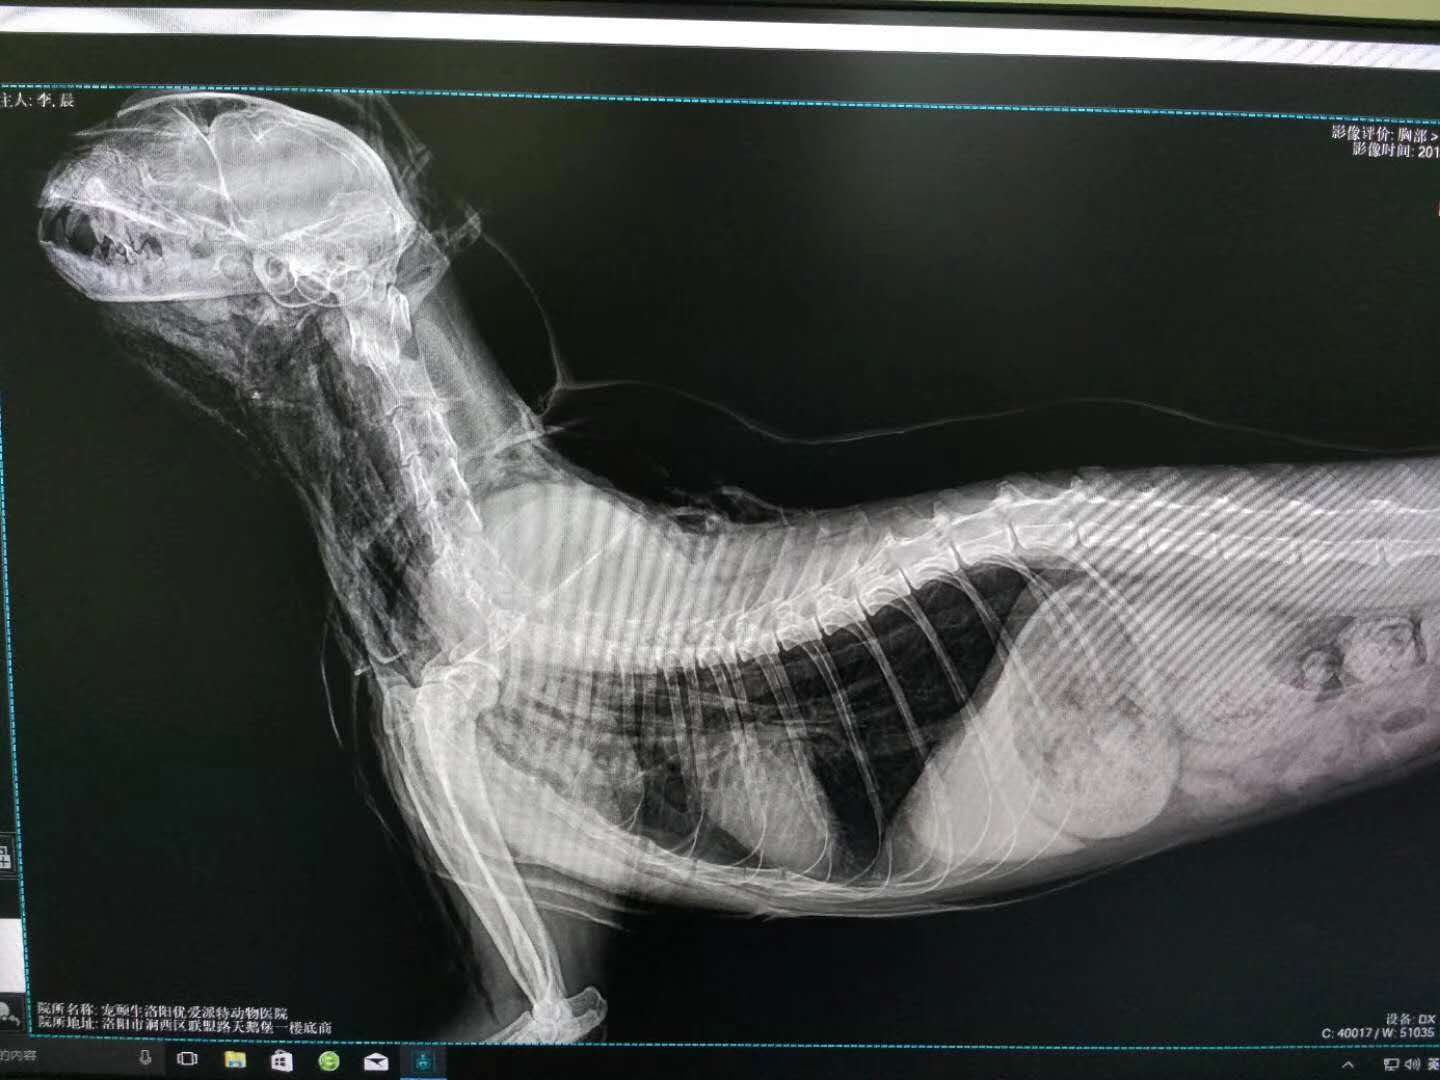

轉(zhuǎn)院全身氣腫病例治愈出院:暹羅貓,發(fā)財(cái),近期在其他醫(yī)院做的絕育手術(shù),術(shù)后出現(xiàn)全身氣腫(第2,第3張照片為原醫(yī)院拍攝),轉(zhuǎn)賬至我院,經(jīng)我院檢查發(fā)現(xiàn),在貓咪氣管入胸段,約有5.6mm大小孔洞,氣體延此孔泄露,并移行到頸部背測,接入皮下疏松結(jié)締組織,進(jìn)一步擴(kuò)散至全身。推測可能與絕育手術(shù)呼吸麻醉時(shí)氣管插管不當(dāng)有關(guān)。我院采取壓迫保守療法,住院10天,痊愈出院。PS:寵物主人選擇醫(yī)院時(shí),一定要慎重,就診時(shí)關(guān)鍵是大夫水平,其他是次要因素。